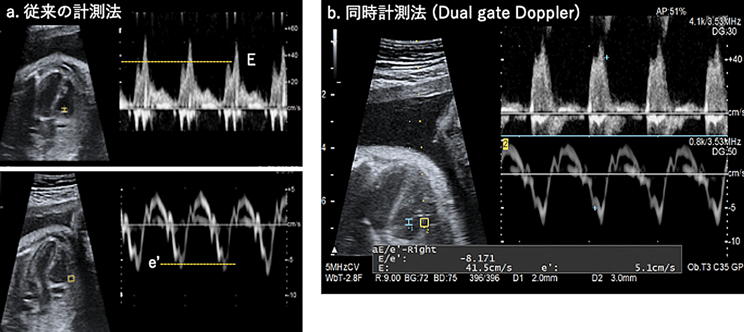

組織ドプラ法(tissue Doppler imaging: TDI):組織ドプラ法による拡張早期僧帽弁輪最大移動速度(e′)は左室弛緩能の指標とされている.左室流入血流速波形のE波は左房圧と左室弛緩能の両者の影響を受けて二相性に変化するが,これを左室弛緩能と一方向性に相関するe′で除したE/e′は左房圧と直線的に相関し,平均左房圧の推定に用いられる.ここでは従来法(Fig. 4a)と同時計測法(Fig. 4b)について示す.組織ドプラは角度依存性のため,できるだけドプラビームに心室壁が直線的に入るように画像を記録する.胎児においても多用されており,双胎間輸血症候群の受血児13)や重症な胎児発育不全においてE/e′の上昇が報告されている14)

Pediatric Cardiology and Cardiac Surgery 40(2): 103-112 (2024)

Fig. 4 組織ドプラ法(tissue Doppler imaging: TDI)